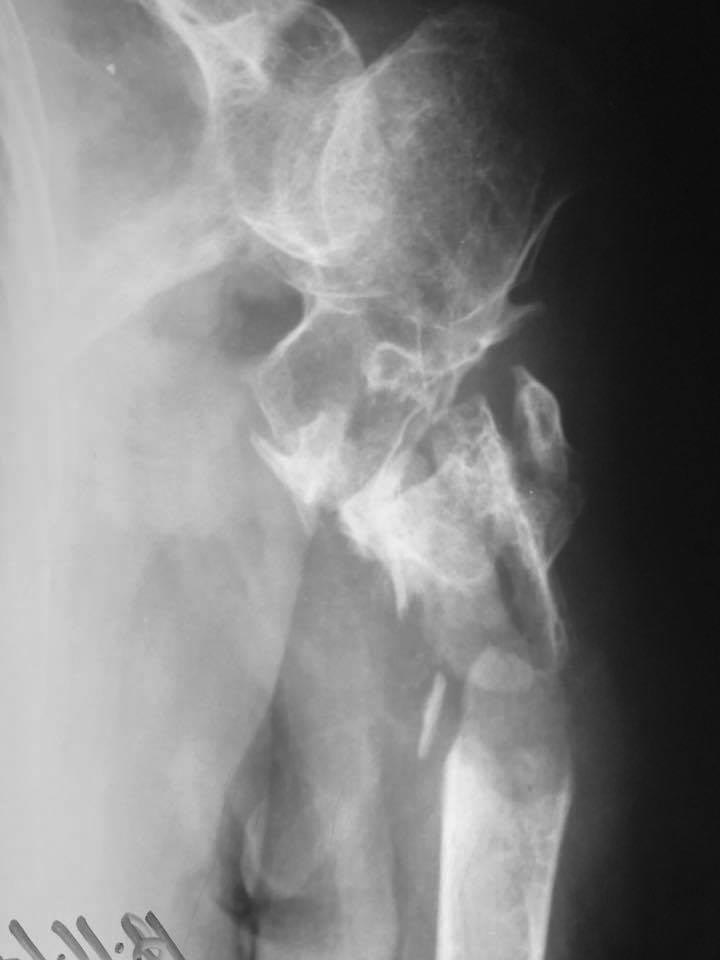

[Ortho] Новый перелом на фоне несращения плеча

Уважаемые коллеги, подскажите ...... в принятии решения? Первая травма 2

года назад. Вторая 2 недели.